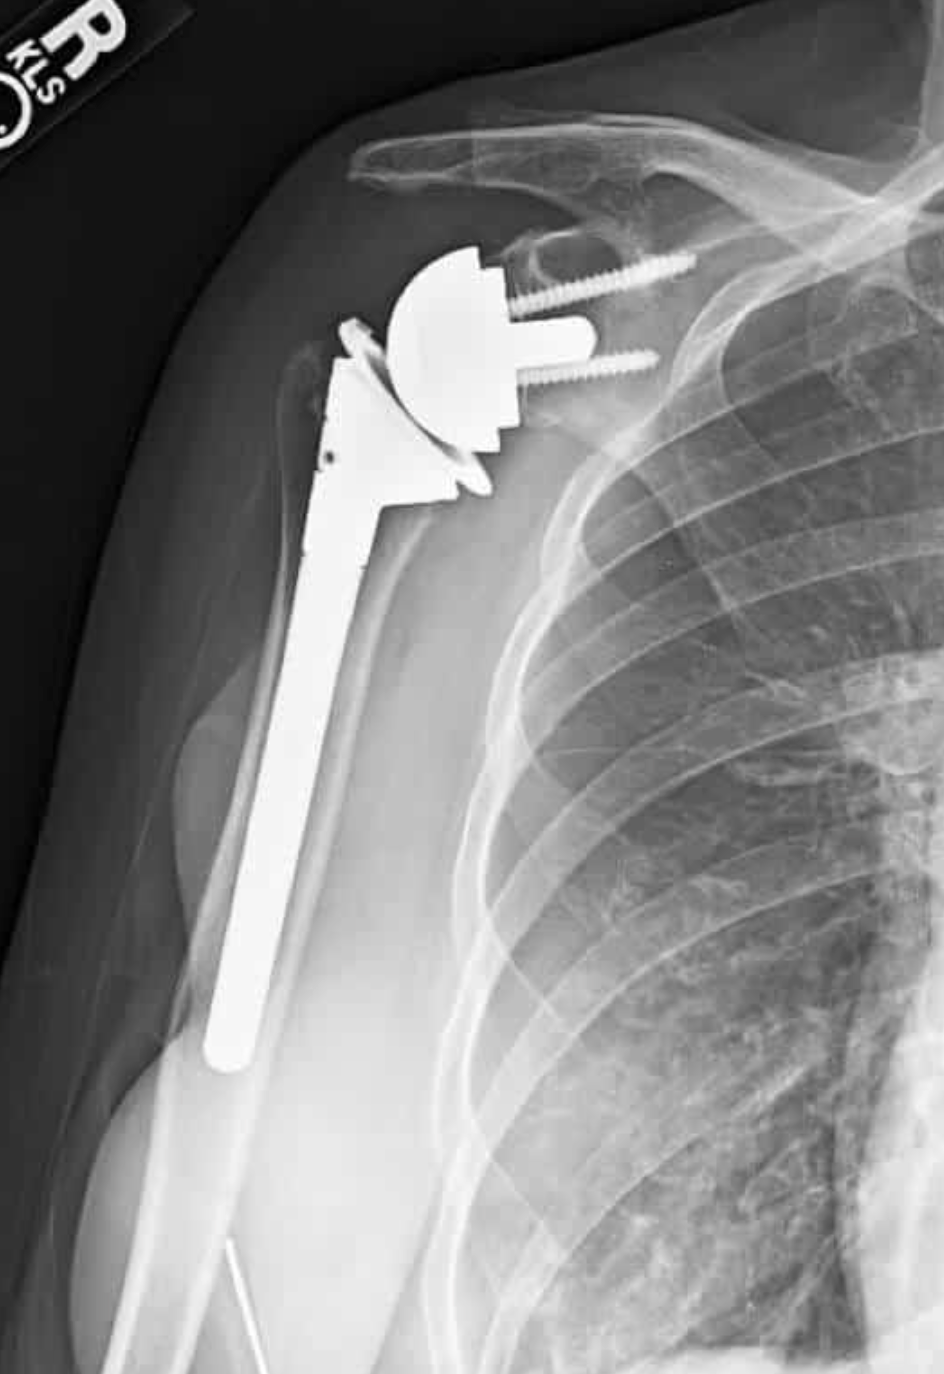

Anatomic Total Shoulder Arthroplasty (ATSA):

- This surgery replaces the shoulder joint with parts that mimic your natural anatomy—a new ball (humeral head) and socket (glenoid).

- ATSA works best if your rotator cuff (the group of muscles and tendons that stabilize your shoulder) is healthy and strong.

- It is usually recommended for younger, active patients with osteoarthritis or other types of shoulder arthritis, and no major damage to the rotator cuff.[1][2][6][7][4]

- ATSA often provides better rotation and overall movement when the rotator cuff is intact.[1][8][6][9]

- However, if the rotator cuff becomes weak or tears after surgery, the artificial socket may loosen over time.[1][9]

X-ray image of a shoulder with an anatomic total shoulder arthroplasty